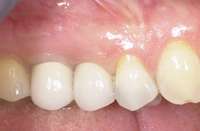

Figure 1G Radiographic confirmation of bone regeneration 8 months after surgery. Figure 1H Radiographic confirmation of implant osteointegration into the new bone 14 months after the initial surgery. Figure 1I. Final implant-supported restoration.

Figure 4C Radiographic view of implant placed simultaneously with sinus bone grafting in site No. 3. Figure 4D Radiographic confirmation of the re-establishment of the sinus floor. Figure 4E Final implant-supported restoration.